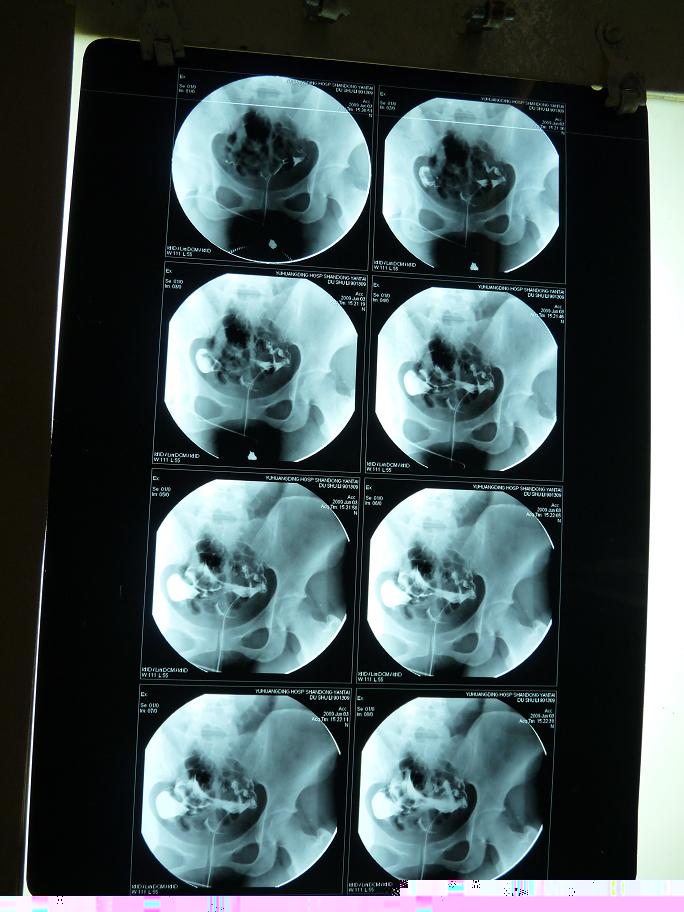

以下是引用黑白光影在2009-6-6 9:58:00的发言:[br]左侧输卵管粗细不均、僵硬、通而不畅,右侧输卵积水。